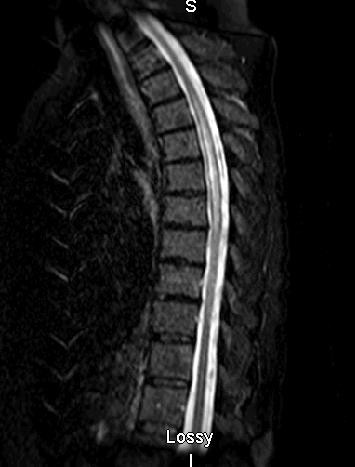

But subtle differences distinguish NMO from MS: NMO attacks are generally more severe and sometimes fatal. Both diseases involve central nervous system (CNS) lesions, which can be seen by MRI, but in NMO patients, these lesions are typically found on the spinal cord (often affecting three or more vertebral segments) and optic nerves, whereas MS often affects other brain areas. And while MS is more common in temperate zones of both hemispheres, NMO seems to equally affect individuals from different ethnic groups and climates. That’s why, among people from the West Indies and Asia, NMO appears to be a quite common cause of demyelinating disease, while it is far less common than MS among white people in North America, Europe, or Australia. (In the U.S., only about 4,000 to 10,000 people have been diagnosed with NMO, compared with an estimated 400,000 with MS.)